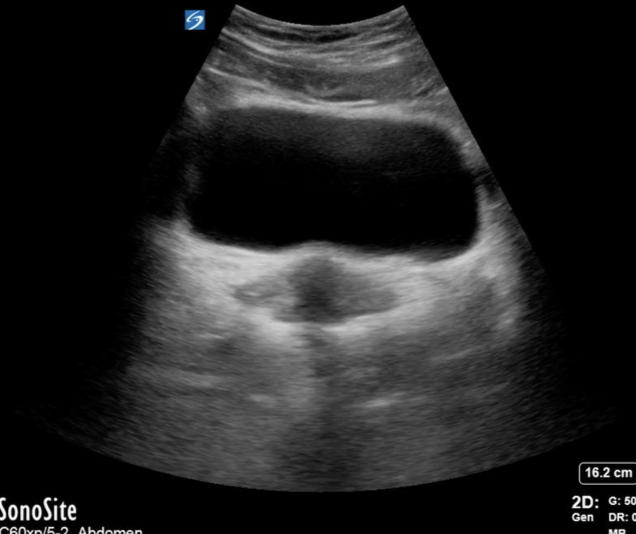

Probe: Curvilinear Preset: Pelvic / Abdomen Position: Supine, bladder moderately full

1️⃣ Start as for a trauma E-FAST bladder view (transverse suprapubic).

2️⃣ With the bladder in near field and uterus in far field, rock the probe tail → left to find the right ovary.

3️⃣ Reverse direction to visualize the left ovary.

Appearance: Oval, isoechoic or mildly hypoechoic stroma with anechoic cystic follicles.

Location: Just lateral to the uterus and medial to the internal iliac vessels.

- Begin as if you were scanning the bladder in a trauma E-FAST.

With the probe in the transverse position, gently rock the probe’s tail toward the patient’s left to bring the right ovary into view. It may require a little cephalocaudal sweeping to find the ovary.

To visualize the left ovary, use the same approach in the opposite direction by rocking the tail toward the patient’s right

- The normal ovary will appear as an oval structure with an isoechoic, if not slightly hypoechoic stroma (the supportive connective tissue surrounding the follicles) and variable anechoic cystic follicles.

- The ovaries will appear just lateral to the uterus and medial to internal iliac vessels (Schwimer, 1985).